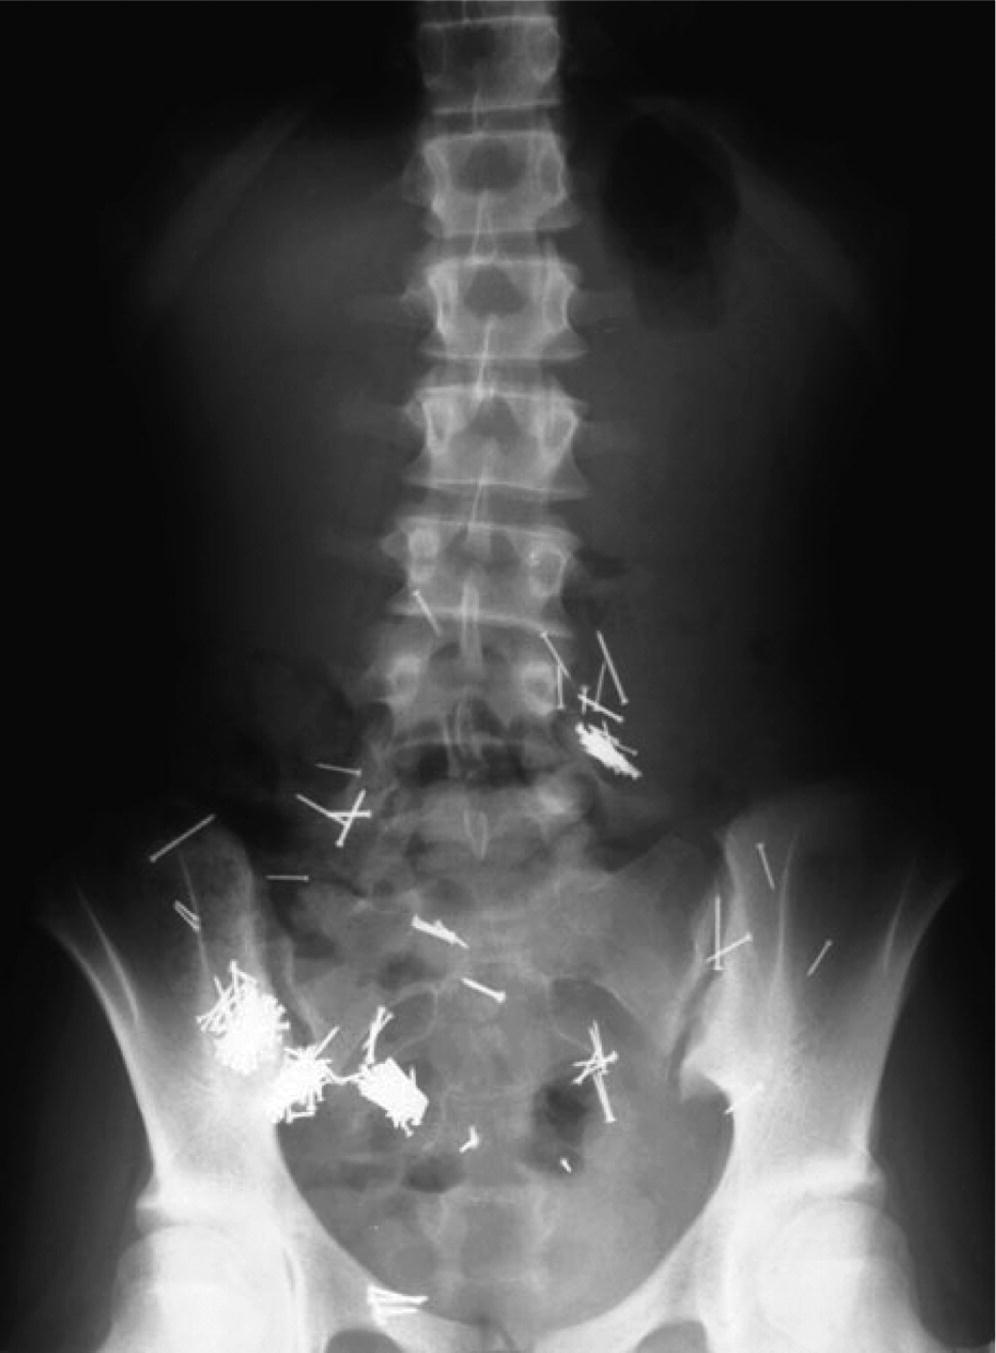

Völlig anders ist die Situation bei Drogenkurieren die zum Beispiel Päckchen voller Kokain verschlucken. Gegenstand fällt runter und ist wie vom Erdboden verschluckt. Meine Tochter 16 Monate hat einen Nagel verschluckt am Sonntag.